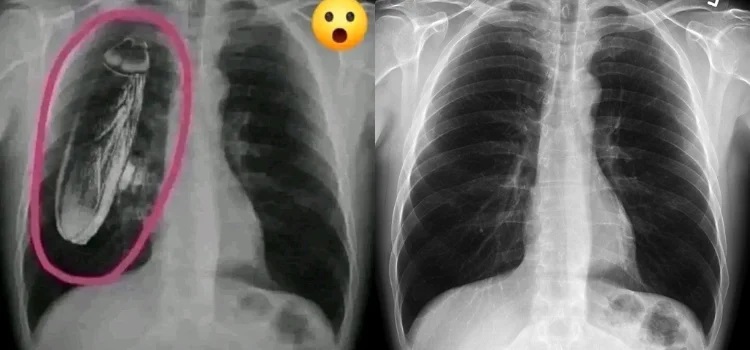

İddiaya eklenen fotoğraf tersine görsel arama yöntemiyle arandığında, “hamam böceğinin” fotoğrafa sonradan eklendiği anlaşılıyor. Fotoğrafın aslı standart bir göğüs röntgeni.

İki görsel karşılaştırıldığında, böceğin sonradan eklendiği de görülüyor.